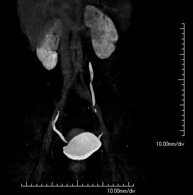

- Aortoiliac CT angiography

A non-invasive diagnostic test that involves examining the iliac arteries and abdominal aorta, obtaining high-definition anatomical images using CT (computed tomography) equipment and iodinated contrast dye. With the aid of workstations specialised for arterial studies, the image quality supports 2D and 3D reconstructions. This test is particularly recommended as a pre-surgical study (vascular map) prior to percutaneous or surgical interventions on the abdominal aorta, as a complementary study in patients with lower limb ischaemia, etc.